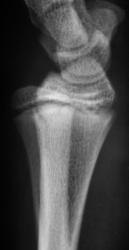

Пациент направлен врачом хирургом в рентгеновский кабинет для рентгенографии лучезапястного сустава. Произведено стандартное исследование. Ваше мнение уважаемые коллеги?

Продольный перелом лучевой кости.

Перелом - эпифезиолиз и продольная трещина в луче, смешение периферического фрагмента к тылу на приблизительно 20 градусов

Перелом луча без смещения. А вообще - головка локтевой кости смущает... или полупроекция?... Доснять бы в/3 предплечья - возможно повреждение Галеацци

В руководстве  Interpreting Trauma Radiographs Jonatan McConell et al. Blackwell Publishing 2005 p. 130 говорится о нормальном угле в боковой проекции в 10 -15 градусов. В представленном наблюдении угол составляет около 95-98 градусов (транспортира под рукой не оказалось), что говорит об угловом смещении периферического фрагмента к тылу на угол от  16 до 23 градусов.